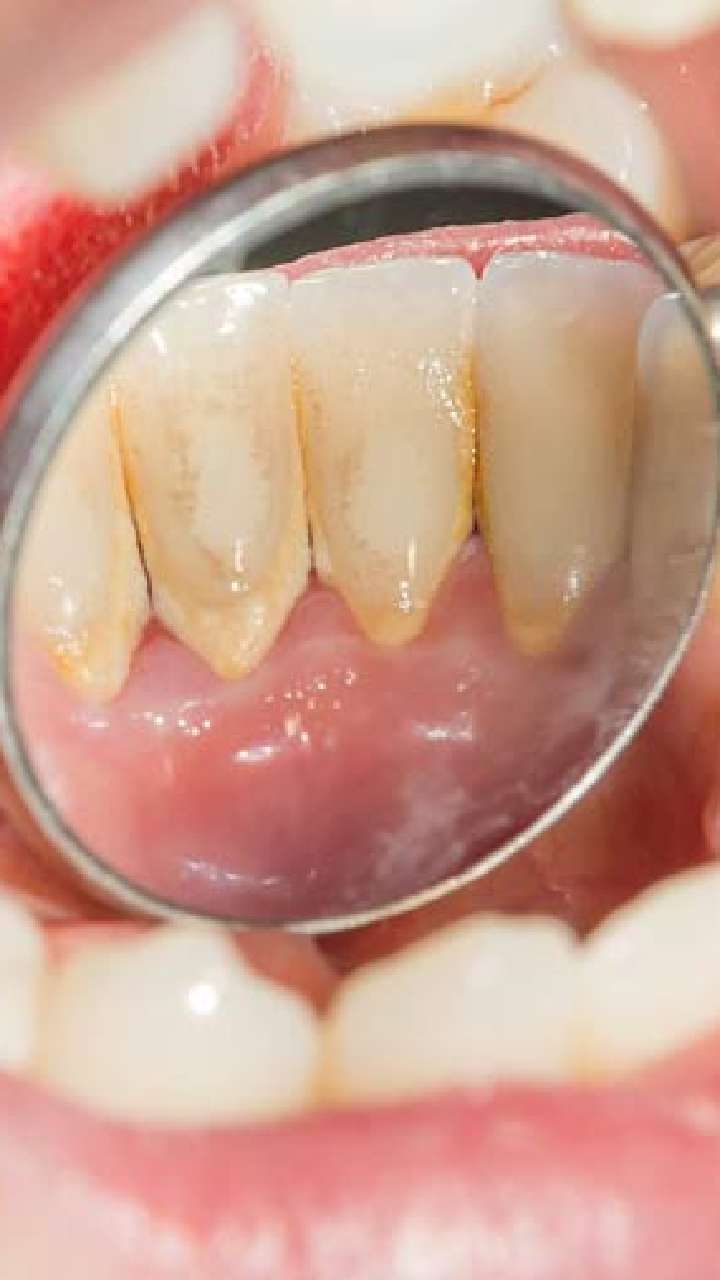

कई फूड आइटम्स और ड्रिंक्स ऐसे होते हैं, जो दातों में प्लाक बनाने का कारण बन सकते हैं और आपके दांतों पर गंभीर स्वास्थ्य प्रभाव डाल सकता है।

मसूड़ों की बीमारी

प्लाक एक बैक्टीरिया से भरी चिपचिपी फिल्म है, जो मसूड़ों की बीमारी और दांतों की सड़न में मदद करती है।